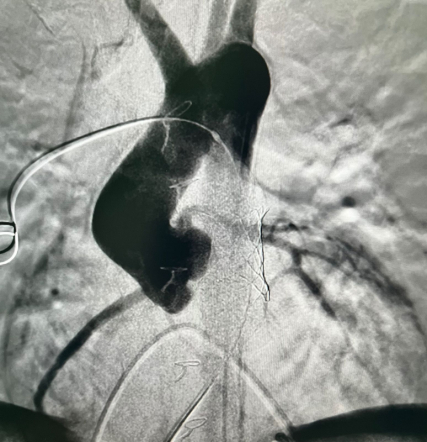

У пациента из Луганской Народной Республики просвет ранее имплантированного кондуита составлял 1,5 сантиметра, поэтому рентгенхирурги на первом этапе расширили его методом баллонной дилатации. При этом был риск разрыва сосуда, поэтому, чтобы избежать возможных осложнений, медики сначала имплантировали стентграфт – металлический каркас, покрытый герметичным полимером. Просвет кондуита удалось расширить до необходимого диаметра. Затем через бедренную вену хирурги доставили к сердцу искусственный биологический клапан лёгочной артерии Myval индийского производства.

Сложную операцию провела команда врачей Педиатрического университета - рентгенэндоваскулярные хирурги Михаил Комиссаров, Владимир Приворотский и Иван Алешин. Неоценимую помощь медикам СПбГПМУ оказал заведующий отделением рентгенэндоваскулярных методов диагностики и лечения  Городской многопрофильной больницы №2 Евгений Шлойдо.